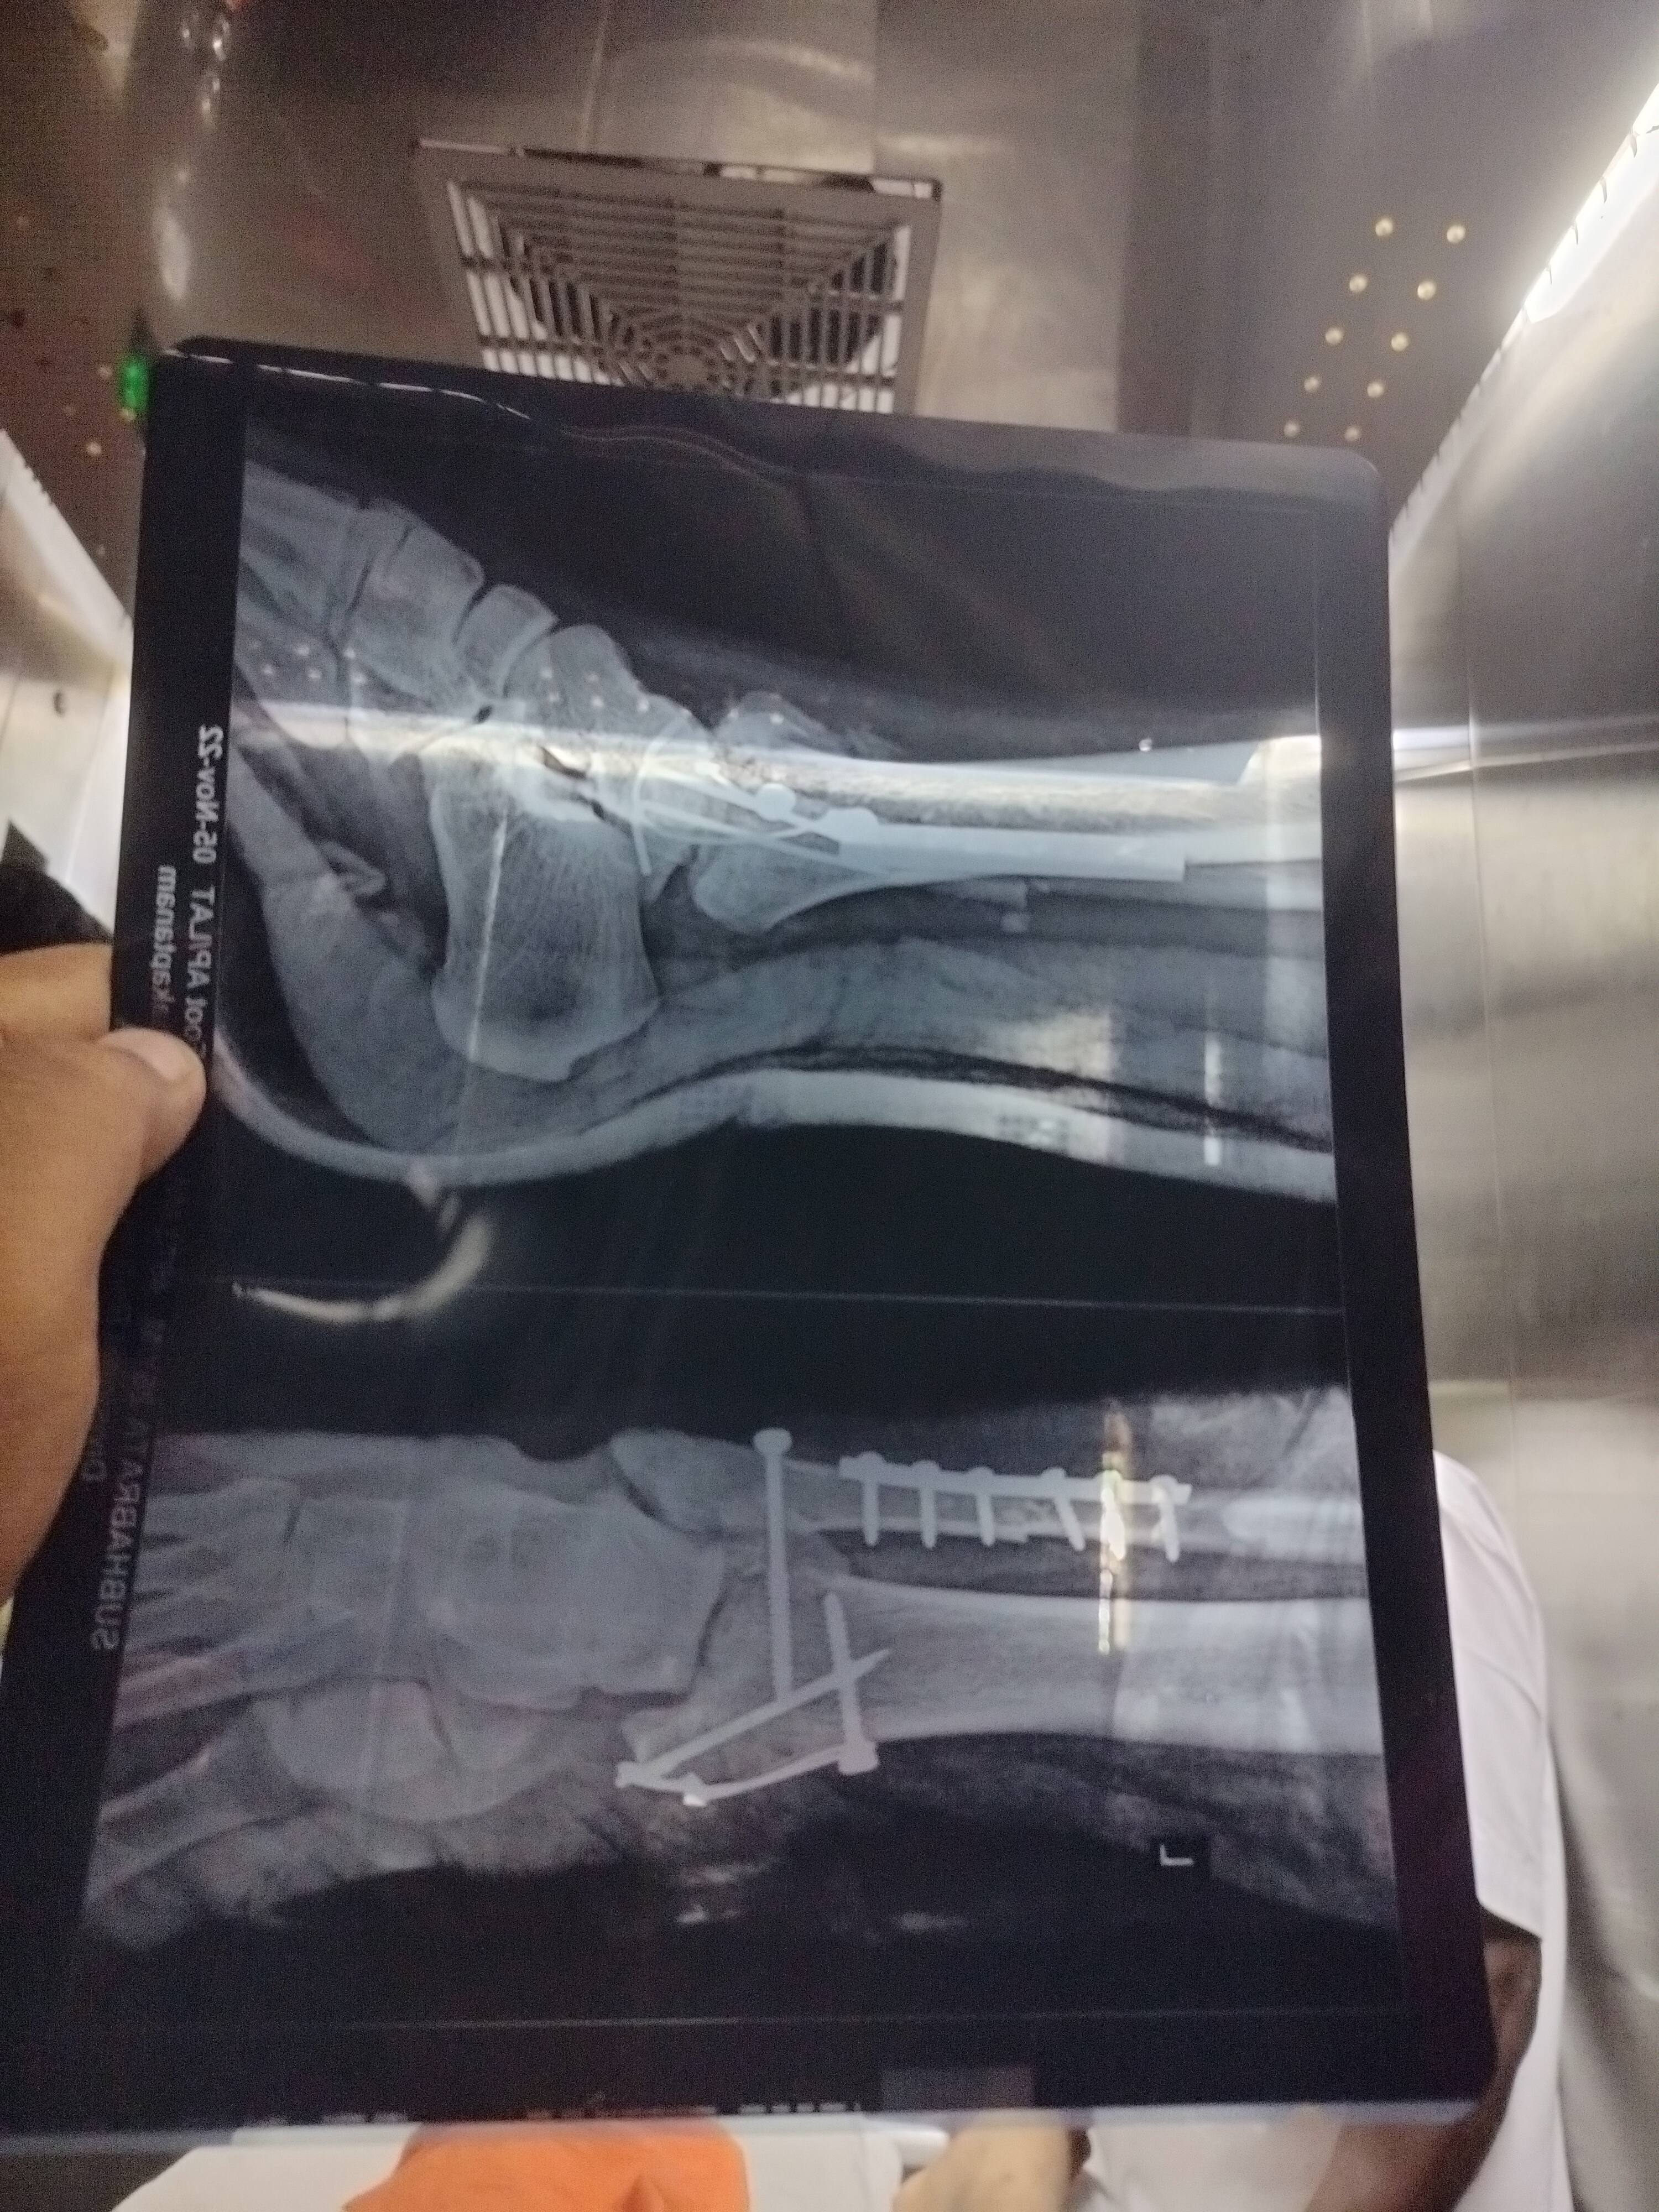

Surgery done sir.my age is 25 how much time required to recover sir

I would say 3 to 4 months will take for complete union . You can take calcium for faster healing . Where did you got this surgery ?